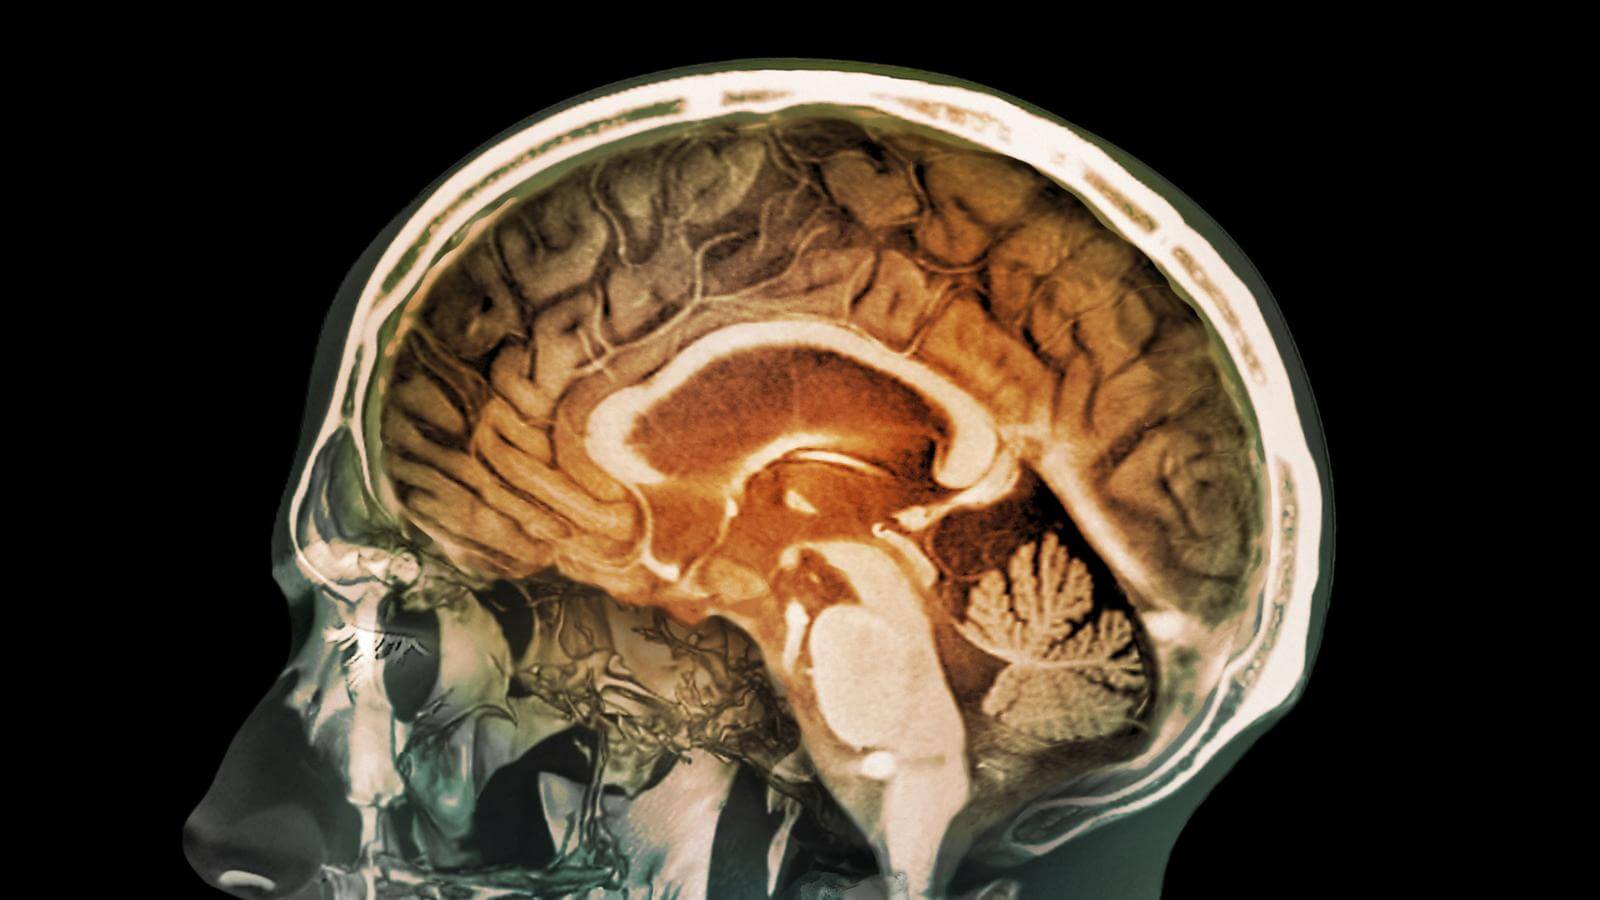

В 1970-х годах Годфри Хаунсфилд, инженер фирмы EMI — более известной как дом лейбла The Beatles — нашел способ заглянуть в мозг с помощью рентгеновских лучей, более известный как КТ-сканер. Отчасти миллионы, заработанные «битлами», помогли создать эту технологию (хотя некоторые утверждают, что КТ-сканер сделал куда больший вклад).

В Музее наук хранится один из первых в мире КТ-сканеров. Он довольно большой.

Сегодня новейшая технология для сканирования мозга называется функциональной магнитно-резонансной томографией, или фМРТ. Корреспондент BBC встретился с неврологом Джо Девлином из Университетского колледжа в Лондоне, где получил возможность отсканировать мозг с объяснениями.